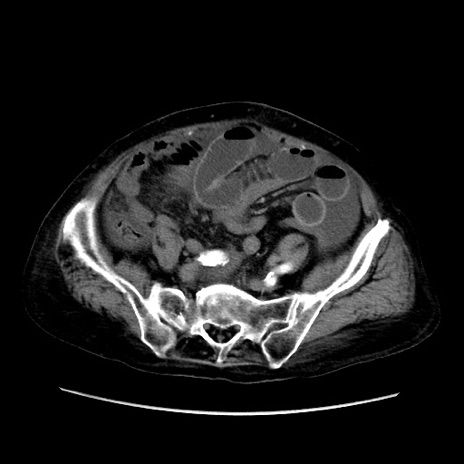

矢状断像

【症例】80歳代 女性

【主訴】腹部膨満感

【現病歴】他院にて肝硬変にてフォロー中。1週間前から便秘、腹部膨満感、臍部腫瘤あり受診となる。

【既往歴】肝硬変

【身体所見】腹部膨隆あり、皮膚変化なし、疼痛なし。

【データ】WBC 4600、CRP 0.25